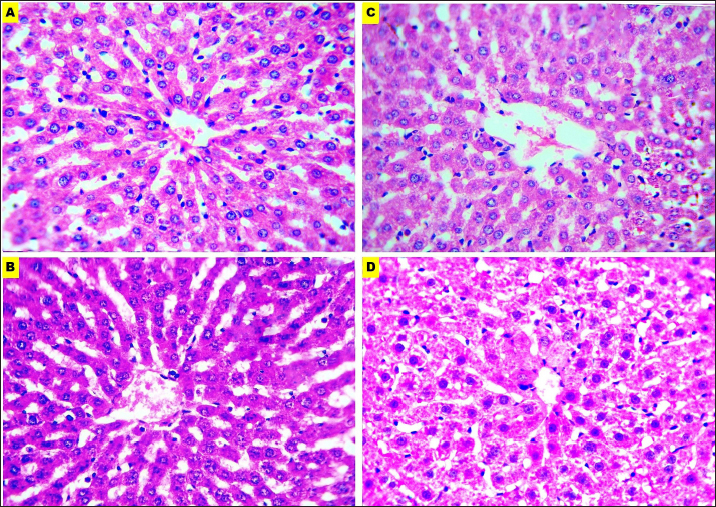

The microscopic evaluation of the liver, kidney, brain, and small intestine sections was analyzed to assess the adequacy of fixatives, the parameters of staining affinity, cellular outline, cytoplasmic attributes, nuclear attributes, and overall structural evaluation were targeted.

EZAT solution showed a significantly higher staining affinity with hematoxylin and eosin particularly in the kidney and brain slides. The grade was (very good) compared with (fair) to (good) grades in the formalin-based solutions. There were no significant differences noticed in the slides of the liver and small intestine, and staining grades were closely equivalent.

EZAT solution also was the best for cellular outline demonstration, cellular architecture and tissue details were clearer in the liver, kidney, brain (cerebral cortex), and small intestine sections compared with formalin-based slides. Grades ranged from very good (4 ± 0.21) in kidney to good (3.71 ± 0.47), (3.71 ± 0.47), and (3.43 ± 0.57) in liver, brain, and small intestine with EZAT slides, and was the worst with formalin 10% which ranged from fair (2.57 ± 0.36), (2.28 ± 0.52), and (2.28 ± 0.35) in liver, brain, and small intestine to poor (1.71 ± 0.28) in kidney.

According to evaluators, the cytoplasmic attributes were also enhanced in the EZAT solution, and the grade ranged from very good (4.14 ± 0.69), (4.14 ± 0.26) in kidney and brain sections to good (3.71 ± 0.47), (3.57 ± 0.36) in liver, and small intestine slides. Statistical differences were noted between EZAT and formalin-based fixatives in kidney and brain slides, while there were no differences observed in liver and small intestine slides. Furthermore, the nuclear attributes were superior with EZAT solution compared with formalin-based fixatives, and grades were significantly different in the kidney, brain, and small intestine, varying from very good (4 ± 0.43) in the kidney to good (3.85 ± 0.50), (3.42 ± 0.57), and (3.28 ± 0.42) in the brain, small intestine, and liver.

The overall structural evaluation revealed excellent microscopic appearance with EZAT slides across all types of tissues, characterized by less tissue disintegration, fine cellular details, sufficient nuclear staining, and improved morphological presentation, grades for this parameter were between 4.28 and 4.14 in the kidney and brain slides, which is significantly better than formalin 10 % and NBF (Figs. 47; Table 1). These results suggest that EZAT provides better tissue preservation and staining quality compared with traditional common fixatives.

Fig. 4. Microphotographs of Hematoxylin and eosin-stained liver sections preserved in different fixatives included, formalin 10% (A), NBF (B), formalin 4% (C), and EZAT solution (D) at 400x magnification.

Fig. 5. Microphotographs of Hematoxylin and eosin-stained kidney sections preserved in different fixatives included, formalin 10% (A), NBF (B), formalin 4% (C), and EZAT solution (D) at 400x magnification.